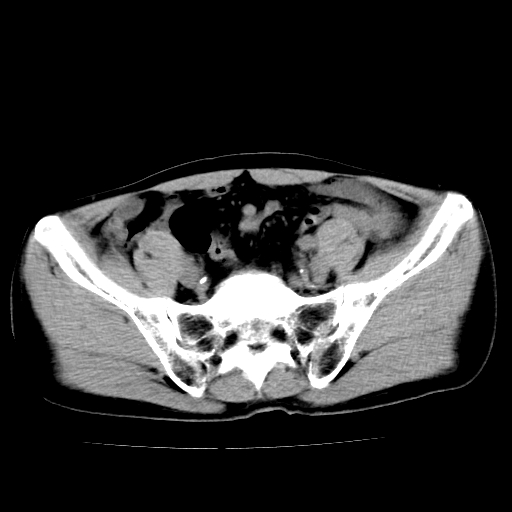

男,47岁,左输尿管结石碎石治疗后10余日。彩超示:左输尿管下段狭窄、输尿管积水。请各位讨论一下左输尿管下段结石还是静脉石?

象是第二狭窄处结石伴以上输尿管、肾盂轻度积水。

输尿管结石伴以上输尿管、肾盂轻度积水。

两侧髂总动脉壁斑状及点状钙化.左侧输尿管行经与左髂总动脉相交后见高密度影,且下段输尿管管腔未见扩张,应该要考虑结石伴以上输尿管及肾盂积水.但右侧结节状高密度影,也应该是结石吧!那以上输尿管未见扩张呢!因此静脉结石可能性也较大.请问楼主碎石前左侧输尿管结石位置.

虽左侧有轻度肾盂积水但不支持结石。1结石边周应该有软组织包绕呈晕征。2钙化点前面见输尿管影也不支持是结石。3彩超没提结石。建议超生复查。

输尿管先位于腹部,后进入盆腔,最后斜穿膀胱壁开口于膀胱,因此,临床上常将输尿管分为腹段、盆段和壁内段。第1个狭窄:在肾盂与输尿管移行处。第2个狭窄:在跨过髂血管处。第3个狭窄:在穿过膀胱壁处。这些狭窄是结石容易滞留的部位。

左侧输尿管有轻度扩张伴有肾盂积水,输尿管下段周围的高密度影不象在输尿管内。

同意,不支持结石。(因显示该高密度影前见扩张输尿管影,另外两侧对称显示)。

左侧高密度影在左侧输尿管的内侧方,所以不考虑输尿管结石.

我认为不是结石的可能性大,因为他的位置和血管钙化的位置邻近